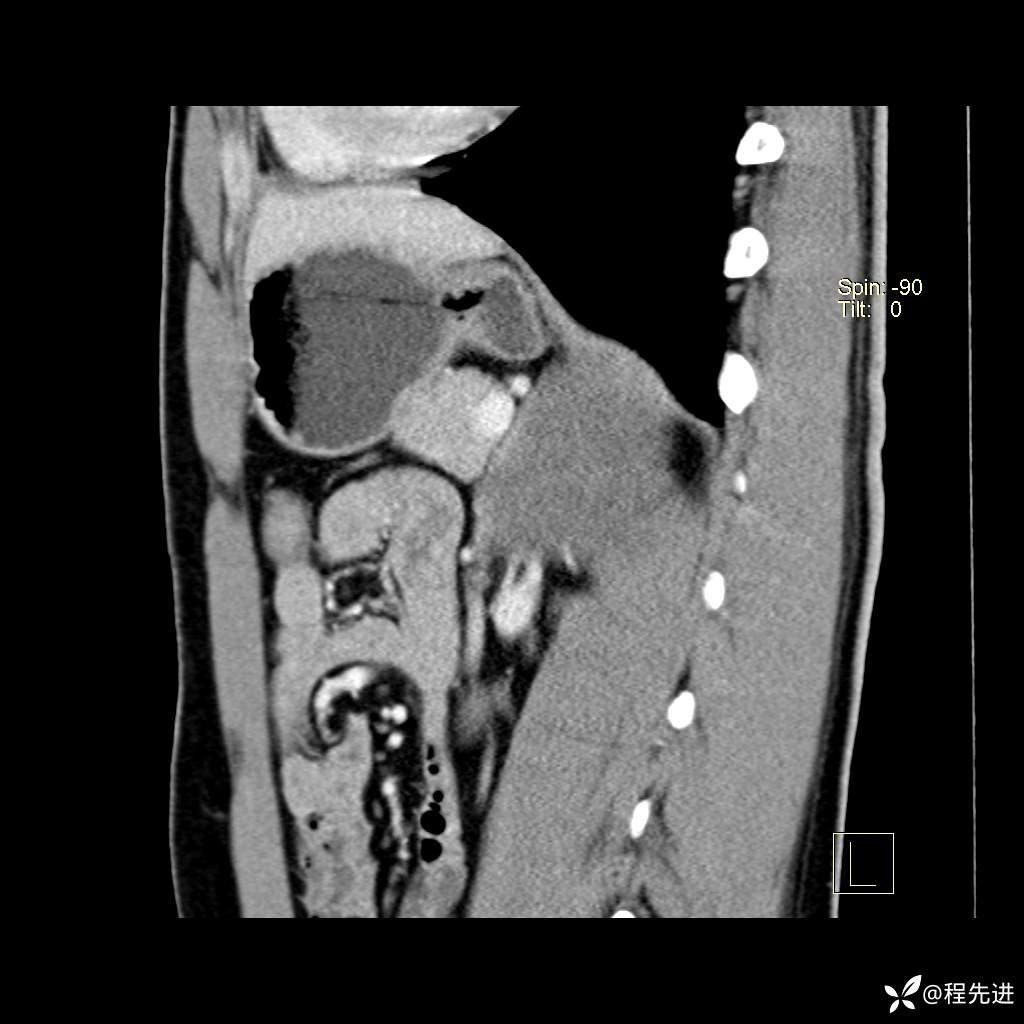

矢状位重建: